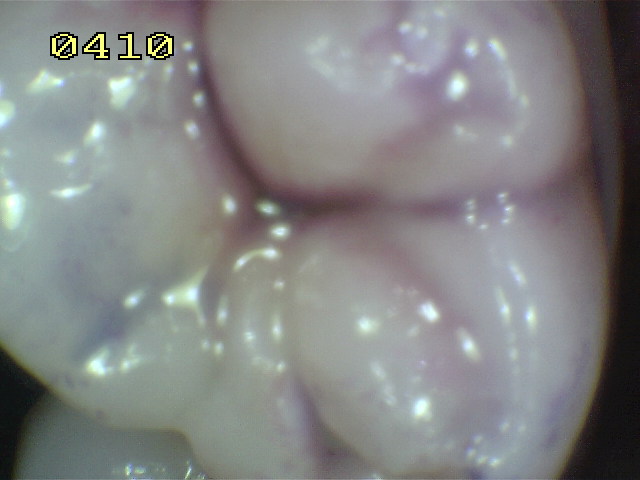

Una morfología de la fisura estrecha, con forma de botella de "Coca-Cola" genera un nicho ecológico ideal para la colonización de cualquier bacteria productora de ácidos. Al no poder remover en forma períodica dicho biofilm de una zona tan estrecha, el ataque ácido genera una lesión cariosa en la dentina, con un aspecto de esmalte intacto a la inspección visual, o sea un típico código 3 y 4 de ICDAS Completo. (Caries Moderada para el ICDAS COMBINADO)

Imagen digital que representa la microfiltración y penetración del sellante realizado.

Microfotografía: Muestra como el sellador obtura la caries subyascente, evitando su avance.

Código 3 (Caries moderada) in vitro. Los códigos 3 in vivo debe ser sellado para evitar el avance del proceso carioso. (MNO)

Código 4 (Caries moderada) in vitro. Los códigos 4 in vivo deben ser tratados en forma operatoria con preservación dental (MOPD), porque presentan dentina infectada.